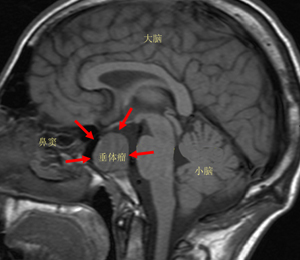

位于我們?nèi)梭w大腦的丘腦下部,有一卵圓形小體,醫(yī)學上稱之為垂體。垂體瘤是一組從垂體前葉和后葉及顱咽管上皮殘余細胞發(fā)生的腫瘤,是良性腺瘤。其主要表現(xiàn)為頭痛、視力障礙、內(nèi)分泌障礙,三者統(tǒng)稱垂體瘤三聯(lián)癥。

垂體僅占大腦體積的1/1000,看似微不足道,卻是人體神經(jīng)內(nèi)分泌的最高指揮中心,分泌5種主要神經(jīng)遞質(zhì)和激素,使全身內(nèi)分泌系統(tǒng)的激素保持在一個平衡狀態(tài)。一旦垂體分泌神經(jīng)遞質(zhì)的機能發(fā)生紊亂,整個內(nèi)分泌系統(tǒng)就會崩潰,過度分泌便形成了垂體瘤。